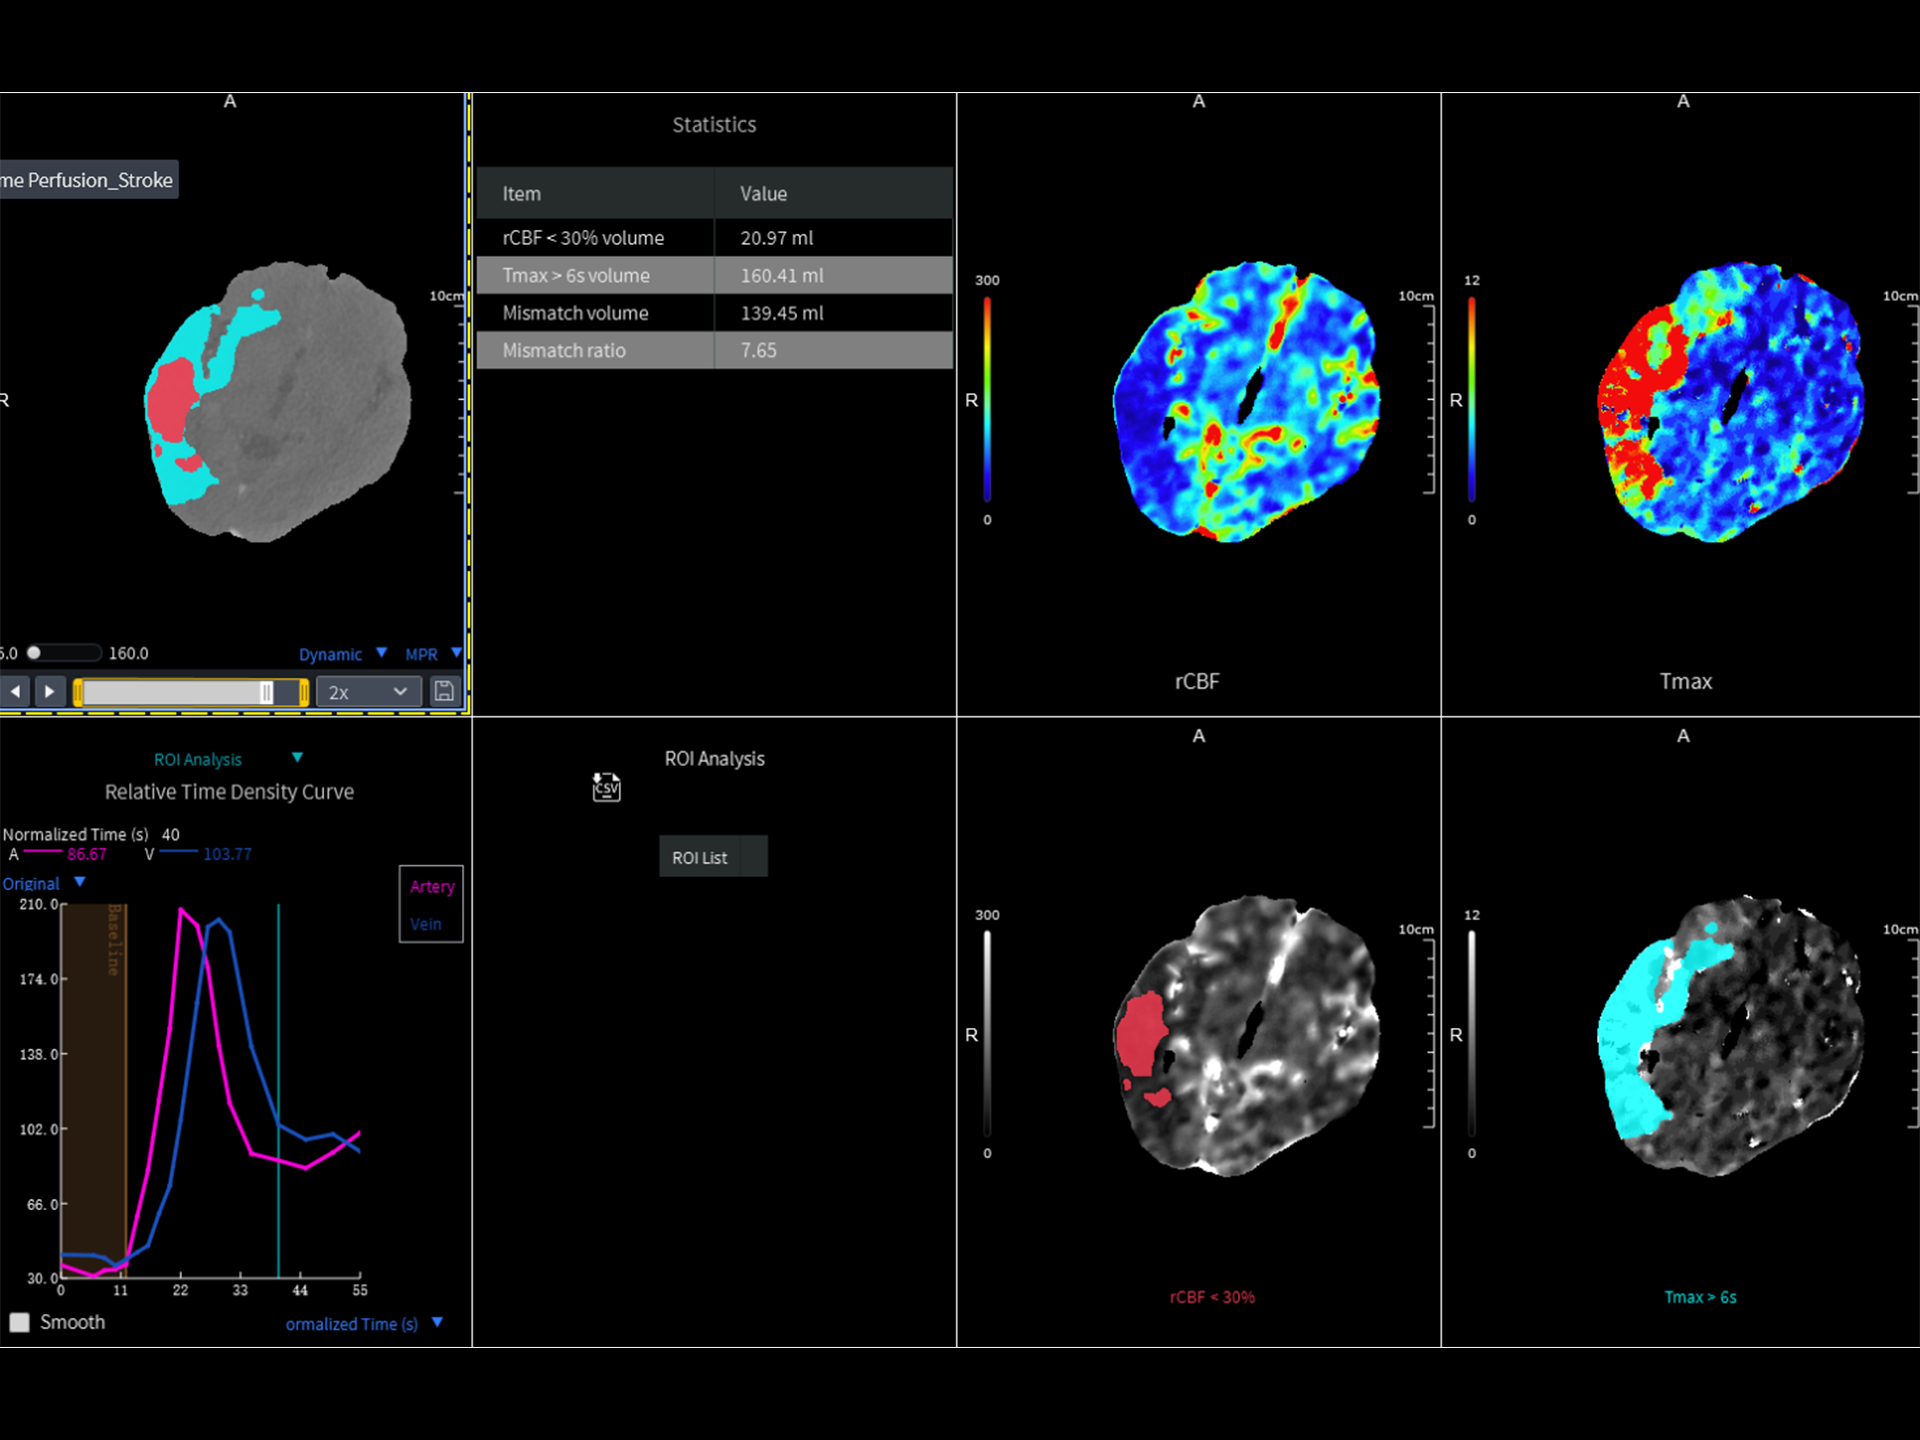

在高端CT系统中,对速度与图像质量的要求早已不局限于常规检查,更延伸至复杂、挑战性更高的临床场景。临床常见的急性病症覆盖多个专科领域,包括心血管、神经系统以及创伤急症。这些领域疾病通常起病突然、进展迅速,对成像速度、覆盖范围、图像质量及诊断效率提出极高要求。

作为高端CT解决方案平台,uCT 868 凭借高速扫描能力、宽体探测器、AI驱动重建算法和智能工作流,能够从容应对上述急症场景下的多部位、多模式联合检查需求。不论是冠脉、主动脉与肺动脉的一站式成像,还是卒中的快速识别,亦或是全身创伤评估中的快速定位与精细结构显示,uCT 868 均能以高速、清晰、低剂量的成像表现,助力临床在关键时刻做出快速而准确的诊断判断,赢得宝贵救治时间。